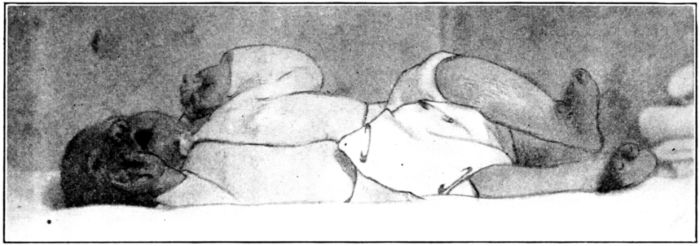

| 177. | Putting the baby in a wet pack | 521 |

| 178. | Baby in wet pack | 522 |